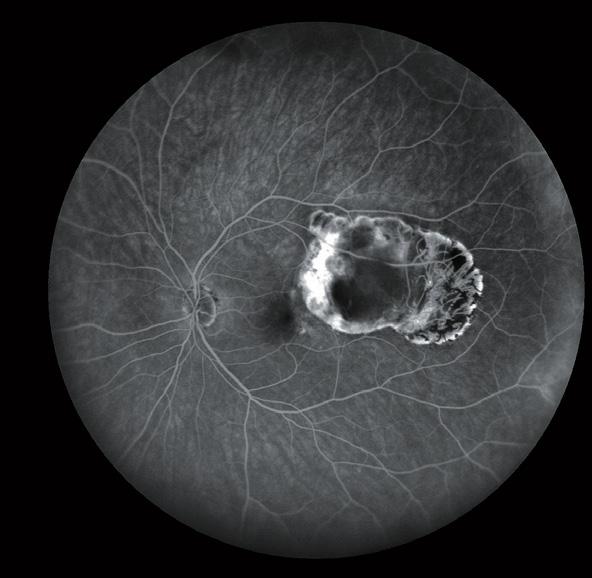

Pneumatic vitreolysis safe and effective in vitreomacular traction. Dermot McGrath reports

Pneumatic vitreolysis seems to be a safe and highly effective technique for treating symptomatic vitreomacular traction (VMT), once careful patient selection is respected, according to Marc Veckeneer MD.

“We have experienced excellent results with pneumatic vitreolysis in cases of focal vitreomacular traction with severe symptoms. For those patients with epiretinal membrane (ERM) or larger macular holes, vitrectomy will probably be required,” he told delegates attending the 19th EURETINA Congress in Paris, France.

In the meantime, evidence on the efficacy of pneumatic traction release is accumulating. In a recent case series of 22 eyes of 19 patients treated with an injection of 0.2 cc C2F6 gas for focal vitreomacular traction with severe symptoms, Dr Veckeneer and co-authors achieved VMT release in 18 eyes (82%) within three months.

Observation is probably the best strategy for those patients with good visual acuity and no or minimal symptoms, while intervention is justified in cases of severe symptoms and visual loss. For patients with concomitant disease such as macular degeneration or diabetic macular oedema, Dr Veckeneer said that the impact of successful traction release on the underlying disease progression remains highly uncertain. Chances of a successful outcome seem higher in cases where the outer retinal and retinal pigment epithelium (RPE) degenerative changes, as seen on OCT, are still limited and in close correspondence to the area of vitreous adhesion.